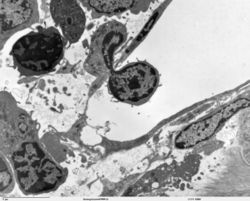

Rudolf Virchow (1821-1902) is generally recognized to be the father of microscopic pathology. While the compound microscope had been invented approximately 150 years prior, Virchow was one of the first prominent physicians to emphasize the study of manifestations of disease which were visible only at the cellular level. A student of Virchow's, Julius Cohnheim (1839-1884) combined histology techniques with experimental manipulations to study inflammation, making him one of the earliest experimental pathologists. Cohnheim also pioneered the use of the frozen section procedure; a version of this technique is widely employed by modern pathologists to render diagnoses and provide other clinical information intraoperatively.

As new research techniques, such as electron microscopy, immunohistochemistry, and molecular biology have expanded the means by which biomedical scientists can study disease, the definition and boundaries of investigative pathology have become less distinct. In the broadest sense, nearly all research which links manifestations of disease to identifiable processes in cells, tissues, or organs can be considered experimental pathology.